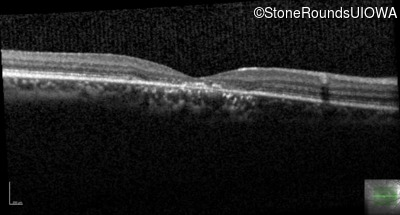

OD

OS

20/125 -2

OCT Stack

20/25 +2